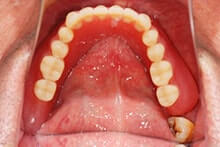

歯の欠損が多い場合